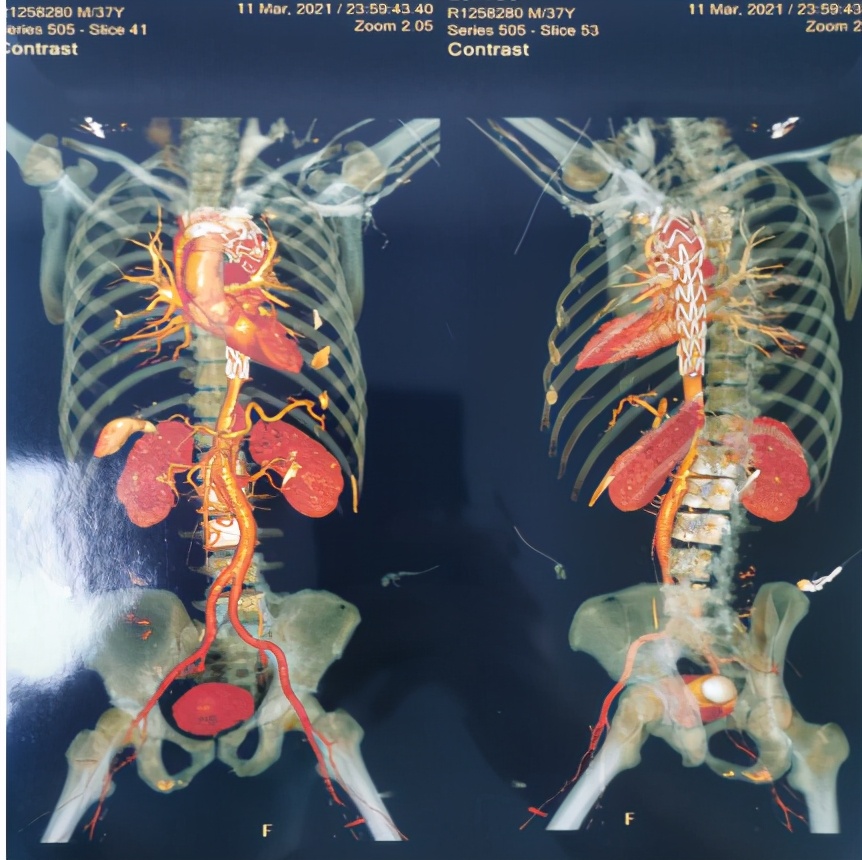

图1、图2为术前患者CTA检查

3月11日,患者血压、脉搏、心率等各项生命监测指标控制良好,病情趋于稳定。罗湖医院血管外科主任黄智勇主任带领团队为患者行胸主动脉造影+胸主动脉腔内隔绝术。术中见主动脉夹层(stanford B型),定位释放支架,精准定位、精确制导,效果立竿见影,无缝连接,假腔完全消失,无内漏,血流通畅(见图3)。

图3